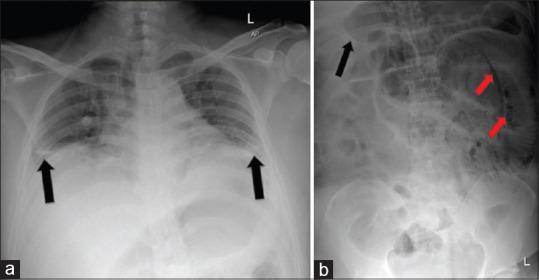

Pneumatosis intestinalis: An important radiological clue in a case of missed perforated appendicitis.

Pneumatosis intestinalis (PI) is a rare radiological finding, characterized by the presence of gas in the bowel wall. It has a wide spectrum of possible underlying diagnosis ranging from benign to life-threatening conditions. We present a case of a previously healthy male who was initially presented with missed diagnosis of acute appendicitis which had led to perforated appendix. Failure to recognize the significance of PI and its correlation with other clinical information had caused the delay in his surgical intervention. Fortunately, the patient made a steady recovery and was discharged well. It is important to have a high clinical suspicion of life-threatening conditions whenever patients presented with a radiological clue of PI. Failure to incorporate this finding with other clinical clues might lead to devastating consequences and delay the necessary treatment.